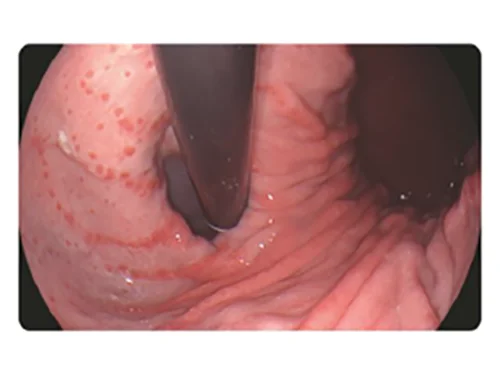

Белый свет

PSI

PSI: Спектральная визуализация цветовой палитрыполихроматическая визуализация

Оптимизация соотношения узкополосного фиолетового и красного цвета на основе белого цвета и использование алгоритмов сложения для повышения контрастности цветов изображения.

Применение

- Повышение вероятности обнаружения поражений, таких как воспаление, атрофия, рак на ранних стадиях, полипы и иные поражения при среднем и слабом увеличении и повышение эффективности обследования.